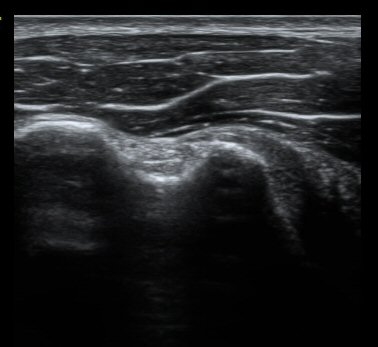

ȸÀü±Ù°³°£°Ý Ⱦ´ã³à°Ë»ç¿¡¼­ ƯÀÌ ¼Ò°ßÀ» º¸ÀÌÁö ¾ÊÀ½(±×¸² 1).

À̵ιڱٰí¶û¿¡¼­ À̵ιڱÙÀÌ Á¤»óÀûÀ¸·Î °üÂûµÇ°í ƯÀÌ ¼Ò°ßÀ» º¸ÀÌÁö ¾ÊÀ½(±×¸² 2).